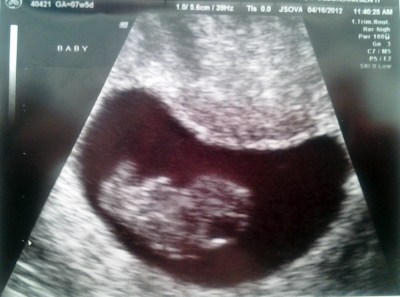

L’altroieri abbiamo fatto la nostra quarta ecografia e ormai no, non c’entra piu’ tutta sotto l’ecografo.

L’ecografista sostiene che nascera’ ciccia come lo era il papa’, visto che ora e’ un chilo e venti e si trova al 6° percentile (vabbe’ sesto, mica ottavo, dai…); la ginecologa dice che invece e’ tutto nella norma. Per noi l’importante e’ che stia bene, e che si faccia sentire, e che la placenta, che e’ ancora un po’ troppo bassa, consenta ad entrambe di arrivare bene ad un parto naturale. E se no faremo la C section e saremo felici lo stesso.